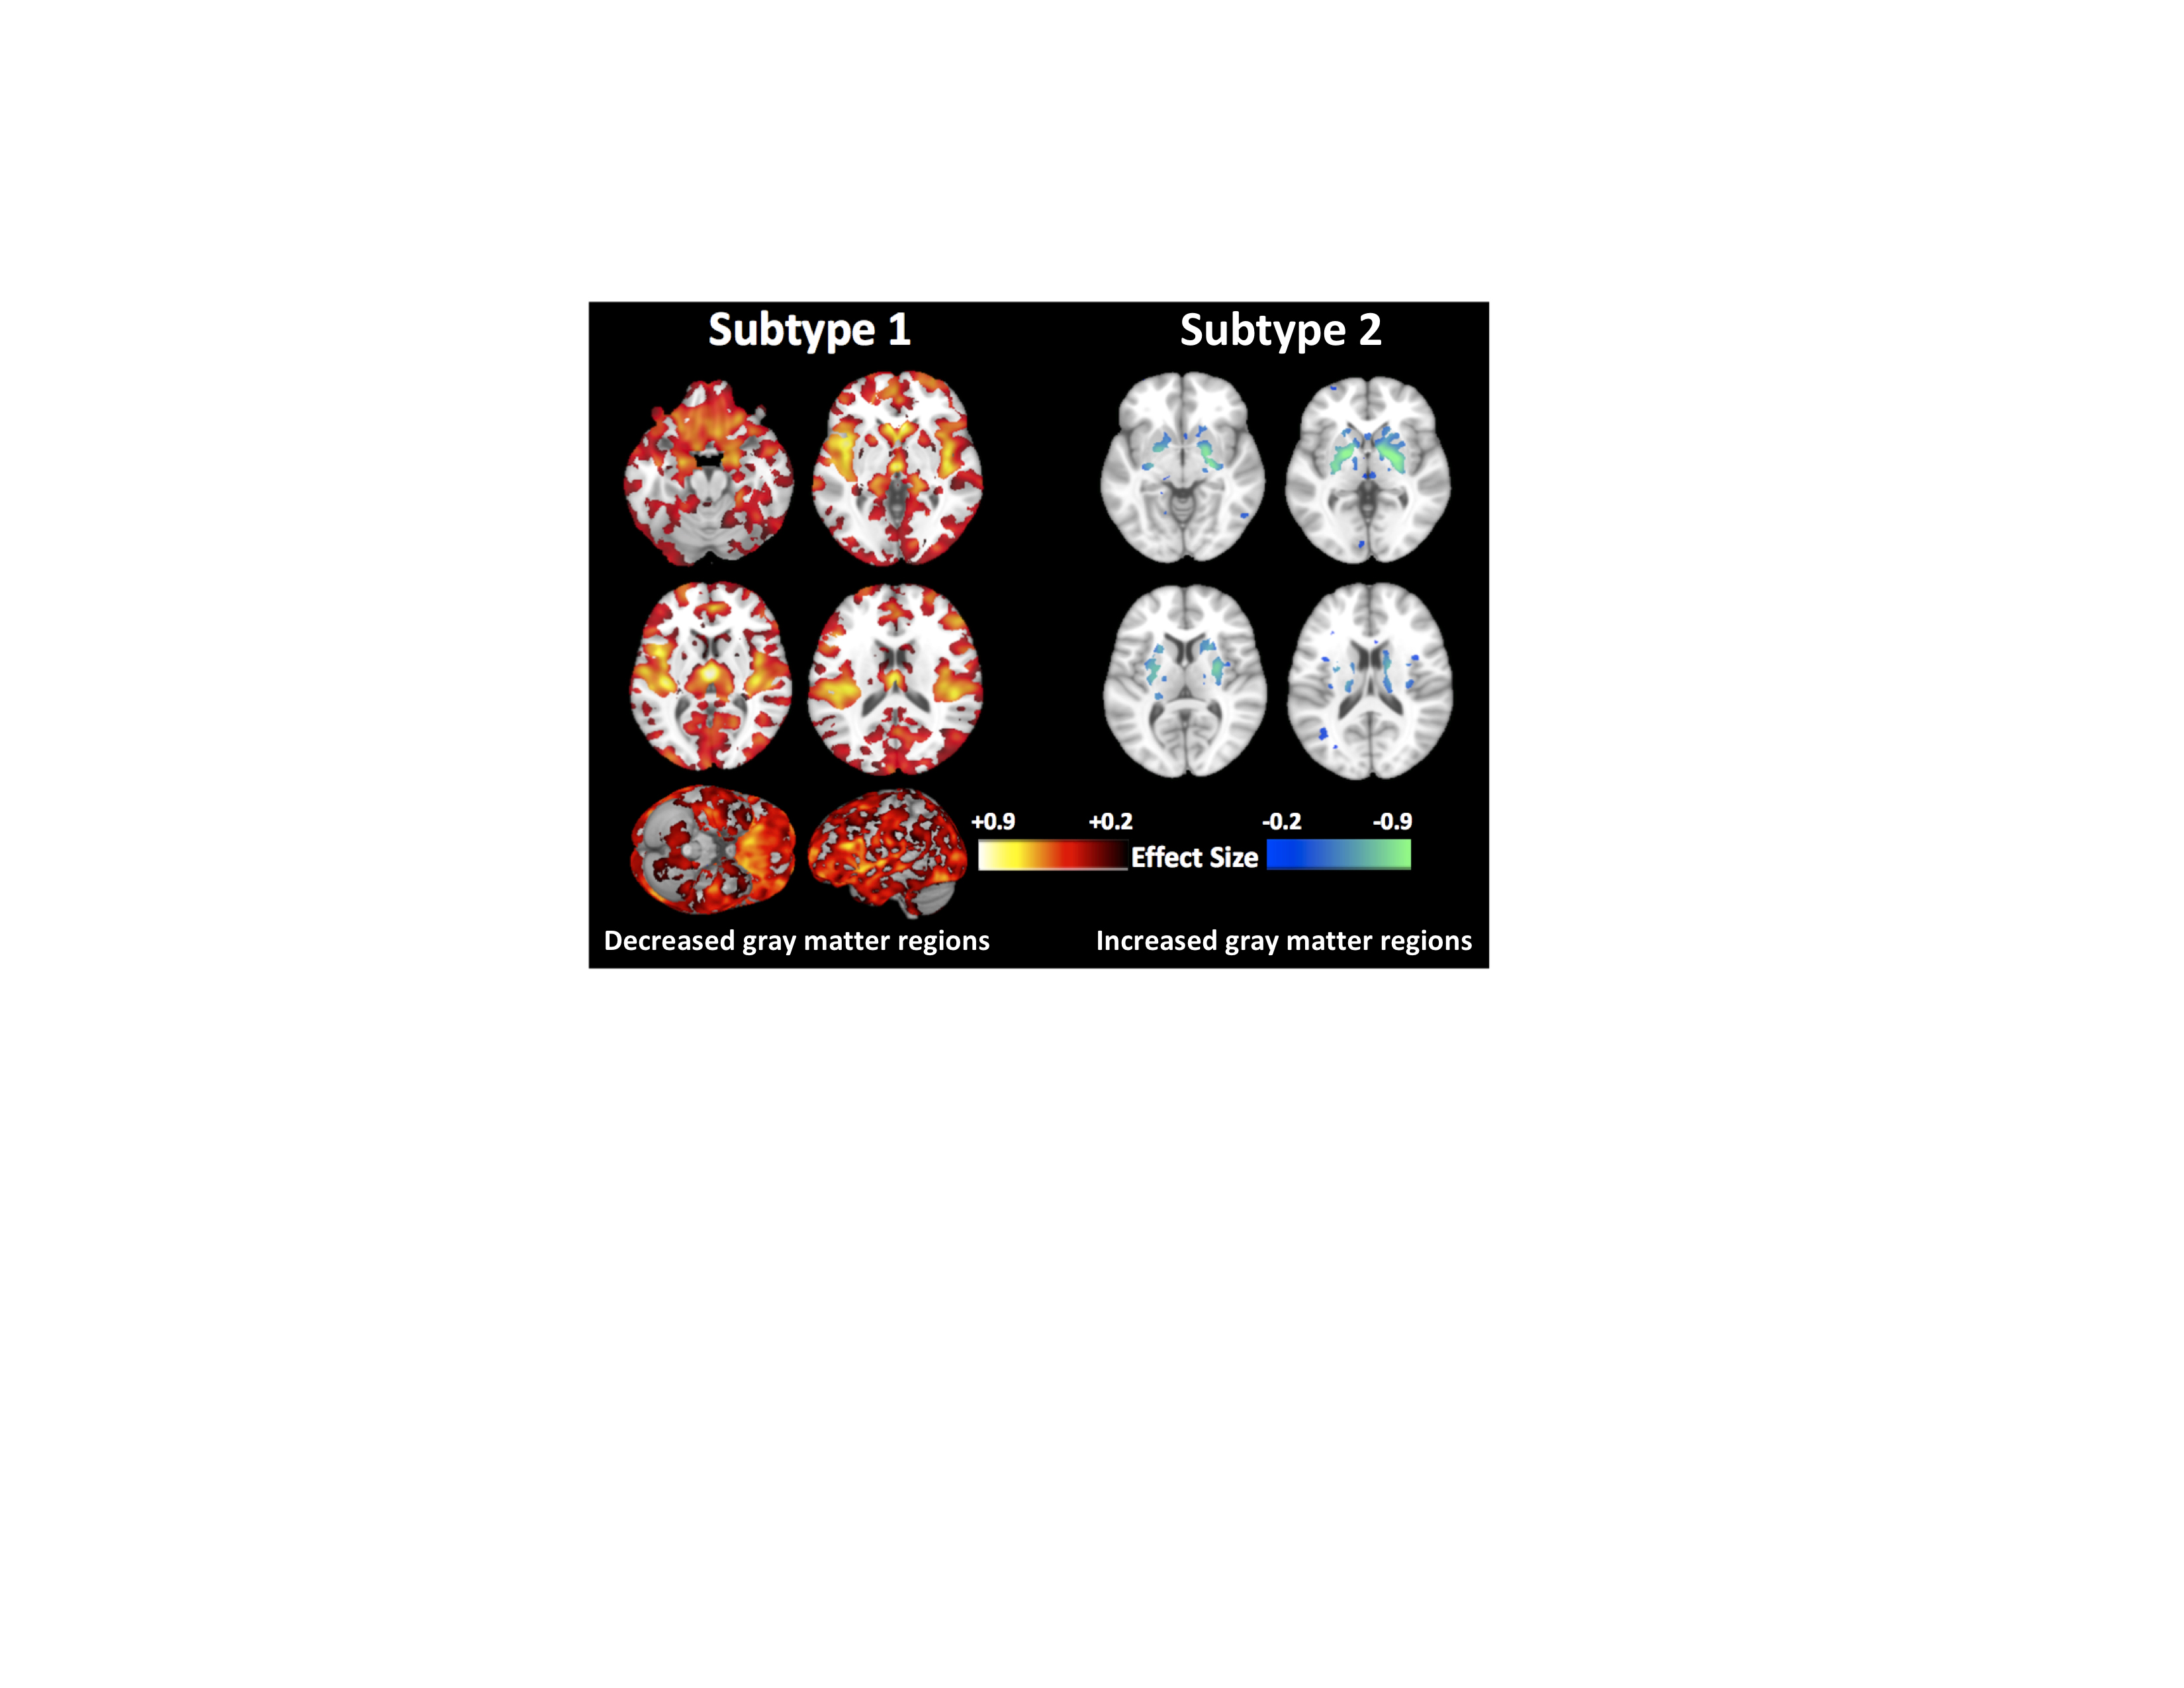

Descubren un segundo tipo de esquizofrenia que puede darse en cuatro de cada diez pacientes

30/04/2020